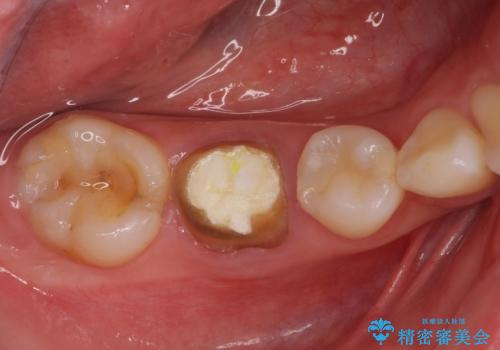

- セラミッククラウンが破損したため、職場近くのクリニックで治療開始したものの、当院への転院を希望して来院された患者様です。

クラウン再製作の際、提案された根管治療を開始したものの、処置の度に痛みを感じるとのことでした。

当院にて根管治療を行った後に、フルジルコニアクラウンにて補綴することとしました。

前医での根管治療の度に感じていた痛みの原因は分かりませんでしたが、元々違和感すらなかった歯であったので、速やかに根管治療を行った後に、ジルコニアクラウンを装着しました。